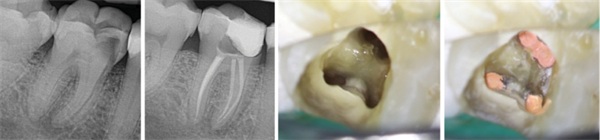

A 60-year-old male patient was referred for non-surgical root canal treatment (NSRCT) of tooth #14. The patient reported no spontaneous pain, and clinical examination revealed an intact full-coverage crown placed approximately one year prior. The tooth was non-responsive to EdgeIce, and periapical radiography demonstrated radiolucencies associated with all three roots. A diagnosis of pulpal necrosis with asymptomatic apical periodontitis was established. Following a discussion of treatment options, the patient consented to NSRCT. He was advised of the specific challenge presented by the severe curvature in the mesial-buccal (MB) root and the associated risk of file separation.

Given the severe curvature, the MB and MB2 canals were initially negotiated and enlarged with hand files (#6 to #10) using quarter-turn, push-pull motions. A mechanical glide path was then established using an R-Glide file in the reciprocating mode of the EdgeApex HP motor. Canal preparation proceeded with a crown-down technique. The MB, MB2, and DB canals were prepared with an R20 file, advancing in 1–2 mm increments with each pass. The P canal was prepared with an R25 file. Further apical enlargement was completed using EdgeSequel Utopia files: 30/.04 for the MB, MB2, and DB canals, and 35/.06 for the P canal. Irrigation with 3% sodium hypochlorite was performed throughout the instrumentation process between each pass of the files.

Following final preparation, working lengths were reconfirmed. Master gutta-percha cones corresponding to the final apical sizes were fitted. The canals received a final irrigation sequence with 3% sodium hypochlorite and 17% EDTA, dried with paper points, and obturated using a bioceramic sealer-based single-cone technique with EdgeBioceramic sealer. EdgePack was used as a heat source to section the gutta-percha points.

The orifices and pulpal floor were sealed with a resin-modified glass-ionomer liner, and the access cavity was temporized with Cavit. The patient was referred back to the general dentist for permanent restoration. A postoperative radiograph confirmed the maintenance of original canal curvature and appropriate length control (Fig. 5).

Fig. 5: The pre- and post-op radiographs of tooth #14 as an example of a case with severe curvature prepared with EdgeOne Blaze Utopia R20, and a post-obturation photo of the access cavity showing the MB, MB2, and the DB orifices.